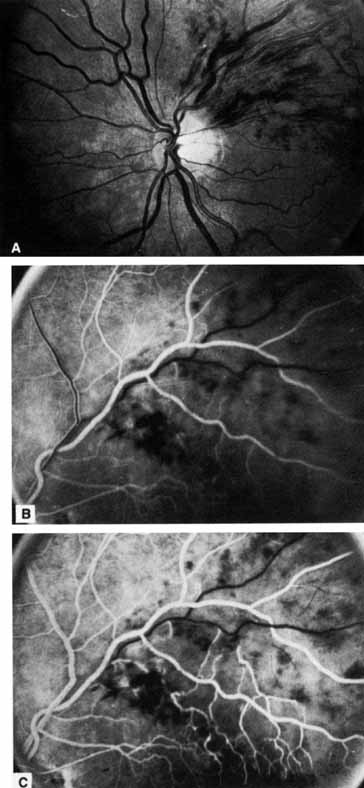

PATHOLOGY Occlusion of the central retinal vein is probably a result of both local and systemic causes. The actual mechanisms producing the clinical picture of central retinal vein occlusion may be roughly divided into those conditions that produce a physical blockage at the level of the lamina cribrosa, and those conditions in which hemodynamic factors result in an obstruction to the flow of blood. These mechanisms probably coexist in many patients with central retinal vein occlusion. The pathogenesis of this condition and the underlying histopathology have remained controversial ever since Michel1 first correlated the clinical appearance with the histopathology. The fact that relatively few eyes have been histopathologically examined during the freshly obstructed stage has contributed to the problem. Many of the reported cases have involved eyes that were enucleated because of long-standing neovascular glaucoma; secondary changes that did not play a role in the original occlusion may have occurred in these eyes. Histopathologic evaluation of eyes removed because of a central retinal vein occlusion demonstrates an occlusion at or just behind the level of the lamina cribrosa.2–7 At this location, certain anatomic factors predispose the central retinal vein to occlusion. First, the lumina of the central retinal artery and central retinal vein are narrower than they are in the orbital optic nerve, and the vessels are bound by a common adventitial sheath.8 Second, the lamina cribrosa is a sievelike, bisecting structure of connective tissue that not only provides support to the optic nerve, but also limits expansion and displacement of the optic nerve and the vessels within it. In 1878, Michel1 found a thrombus in one patient studied. Later, both Coats2 and Harms9 believed, based on their histopathologic findings, that a primary thrombus within the intraluminal portion of the central retinal vein was the most common cause of occlusion. Verhoeff,3 however, was an early advocate of the concept that endothelial cell proliferation was the primary obstructing mechanism, and he believed that thrombosis within the vein did not occur except in patients with sepsis. He believed that most cases diagnosed as thrombosis were actually dissecting aneurysms because he found the intimal lining forced away from the venous wall by the backup of blood in a tributary vein. Klein,5,6 who has done extensive clinical and pathologic studies of central retinal vein occlusion, believes that although primary thrombosis may occur, it is rare. She believes that thrombosis may occur more frequently as an end-stage phenomenon, complicating other initiating mechanisms in the obstructive process. Green and co-workers7 felt that the interval between occlusion and the time of histopathologic study must be considered when interpreting the histopathology of vein occlusion. They studied 29 eyes that were enucleated 6 hours to 10 years after occlusion. As a result of this study, they hypothesized that the flow of blood through the central retinal vein becomes increasingly turbulent as the vein progressively narrows at the lamina cribrosa, where it also may be further impinged on by arteriosclerosis of the adjacent central retinal artery. This turbulence damages the endothelium in the retrolaminar vein, which exposes collagen and initiates platelet aggregation and thrombosis.7,10 Their studies show the evolution of this thrombus. Initially, the thrombus adheres where the endothelium has been severely damaged. Endothelial cell proliferation and recanalization of the vein often occur as a reparative event. Inflammation manifesting itself as phlebitis, periphlebitis, or obliterating endophlebitis is a secondary late-onset factor. Years later, a thick-walled vein with a single channel may occur (phlebosclerosis).7 In some eyes an adjacent, partially obstructed, or narrowed central retinal artery has been observed. This observation is consistent with the prevailing clinical impression that the principal condition associated with retinal vein occlusion is arteriosclerosis. Because the central retinal artery is a true artery, it may be involved in the patchy disease of larger arteries (i.e., atherosclerosis). There is an increased incidence of generalized atheromatous disease in patients who have a central retinal vein occlusion.11,12 As part of this atheromatous change, sclerosis occurs in the common adventitia, which encircles both vessels within the rather rigid support structure of the lamina cribrosa. Compression or constriction of the vein lumen and changes within the vein wall, described as phlebosclerosis, occur. As mentioned, occlusion of the central retinal vein is also influenced by the anatomic confinement of the vein and the artery within the optic nerve, as well as the compactness of the lamina cribrosa and its surrounding connective tissue. Hayreh and co-workers13–16 have investigated the role of occlusion of the central retinal vein and central retinal artery in an animal model. They attempted to produce central retinal vein occlusion in healthy young monkeys by diathermy of the central retinal vessels in the orbit near their entry into the optic nerve sheath. Their study showed that occlusion in the orbit of the central retinal vein alone produced mildly engorged and tortuous vessels and a few retinal hemorrhages; all these conditions returned to normal in approximately 2 weeks. However, when both the central retinal vein and the central retinal artery in the orbit were obstructed simultaneously, a fundus appearance was produced that was “entirely characteristic” of central retinal vein occlusion.13 Later, histopathologic examination of these eyes showed a hemorrhagic infarct of the inner retinal layer. Hayreh and co-workers15 concluded from these experiments that concomitant arterial occlusion is essential in the production of an ischemic central retinal vein occlusion, although its occurrence is possibly only transient,16 and that the site of occlusion is important in determining both the severity and type of occlusion.16 However, this model of occlusion in the orbit of healthy young monkeys may not be comparable to the situation in the aging human, where the occlusion is located at or just posterior to the lamina cribrosa.379 Because fluorescein angiography does not typically show prolongation of arterial filling in central retinal vein occlusion, Fujino and associates17 investigated the role of arterial occlusion by producing central retinal vein occlusion in monkeys using an intravenous injection of neoprene. They were able to show that a primary and complete occlusion of the central retinal vein at the disc produces a secondary artery insufficiency. The ophthalmoscopic appearance produced in monkeys, however, is not identical to the appearance of central retinal vein occlusion in humans. This may be because this technique obstructs all the branch retinal vessels in the peripapillary region, which, in turn, may preclude collateralization.16 McLeod18 noted that in eyes with both a central retinal vein occlusion and a cilioretinal artery occlusion, there was a lack of retinal hemorrhages within the area of retina that was infarcted. He presented this an argument against the combined artery and vein occlusion hypothesis of Hayreh and colleagues.13–16 If an artery occlusion as well as a vein occlusion (combined occlusion) is necessary to produce the typical ophthalmoscopic picture of a central retinal vein occlusion, the retina should exhibit increased hemorrhage in the area supplied by the occluded cilioretinal artery. The histopathologic picture in venous occlusion is now considerably clearer as a result of a series of experiments on branch retinal vein occlusion in the monkey.19–21 This work shows that capillary nonperfusion (ischemia) can result after isolated venous outflow occlusion without the occurrence of primary arterial inflow occlusion (ischemic capillaropathy).22 Although these experiments were performed on branch retinal vein occlusions, there is every reason to believe that the ischemia of the retina seen in central retinal vein occlusion can result from venous outflow disease alone.23 Doppler ultrasound imaging has been used to examine the blood flow in the orbit, including the optic nerve head,24,25 and has been used to examine patients with central retinal vein occlusion.26–28,256,257 As might be expected, the venous velocity in the eye of a patient with central retinal vein occlusion is markedly reduced compared either with the unaffected eye or to control eyes.24,25 There is evidence, however, that the central retinal artery blood flow is also impaired in eyes with acute central retinal vein occlusion.28 In addition, vascular resistance is slightly higher in the ophthalmic artery and short posterior ciliary arteries of both the involved and the clinically healthy fellow eye of patients with central retinal vein occlusion compared with control eyes.28 There is also a trend toward higher vascular resistance of the central retinal artery in the clinically healthy eyes of patients with central retinal vein occlusion compared with control eyes.28 The retinal pathology in an ischemic central retinal vein occlusion consists of a hemorrhagic infarction of the retina that affects primarily the inner retinal layers.29 Neovascularization of the iris and anterior chamber angle can develop; less frequently, retinal neovascularization can also occur.10 This neovascularization is likely related to the unregulated expression of vascular endothelial growth factor (VEGF) in the cells of the neurosensory retinal when affected by the hypoxia in central retinal vein occlusion.329 Later changes include thickening of the retina and reactive gliosis.30 ETIOLOGY The precise etiology of central retinal vein occlusion is not entirely clear. There are now some clues as to the conditions associated with this condition. Many published articles have reported on the association between central retinal vein occlusion and some other condition, whether systemic or ocular. Although some of these associated conditions probably are, in some cases, related to central retinal vein occlusion, there is no way to determine in most cases whether the association is only coincidental on the basis of single-case reports. Any study that attempts to determine either the etiology of or the features associated with central retinal vein occlusion must be a large enough prospective study that it takes into account age- and sex-matched controls and includes a comprehensive, systemic evaluation. Some reports in the literature have been retrospective,31–33 others have had no control group,33–37,258,259,260 and some have not performed a prospective, systemic evaluation.31–34 We are aware of only one prospective, large study of risk factors for central retinal vein occlusion that includes an appropriate age- and sex-matched control group and a standardized, prospective, systemic evaluation.38 The Eye Disease Case-Control Study Group examined 258 cases of central retinal vein occlusion as well as 1,142 controls. An increased risk of central retinal vein occlusion was found in patients with systemic hypertension, diabetes mellitus, and open-angle glaucoma; the risk of central vein occlusion was decreased for patients with increasing levels of physical activity and increasing levels of alcohol consumption (Table 1). For women, the risk decreased with the use of postmenopausal estrogen and increased with a higher erythrocyte sedimentation rate. The authors did attempt to divide the cases into ischemic and nonischemic central retinal vein occlusion. The following conditions all showed a significant association with ischemic cases only: cardiovascular disease, electrocardiographic abnormalities, albumin-globulin ratio, α1-globulin, history of treatment for diabetes mellitus, and blood glucose level. Both systolic and diastolic blood pressure showed significant associations with both types of central retinal vein occlusion, but the odds ratio is greater for the central retinal vein occlusion. Overall, a stronger cardiovascular risk profile was shown for the ischemic type of central retinal vein occlusion.

The prognosis for ischemic central retinal vein occlusion is generally poor because of decreased visual acuity and neovascularization. Visual loss occurs because of macular edema, capillary nonperfusion, overlying hemorrhage (either retinal or vitreal), or a combination of all these. Retinal edema usually gradually subsides except in the macula, where it may persist for many months or years. Macular holes or cysts may form.83,84 Pigment clumping or fine pigment stippling and pigment atrophy are not uncommon, and persistent macular hemorrhage, even years after the occlusion, has been noted.83 Hard exudates often form an irregular circinate configuration around the macula and become more prominent months later. Occasionally an epiretinal membrane may form. In the chronic phase, most hemorrhages gradually disappear over many months; however, scattered, flame-shaped hemorrhages and dot hemorrhages, particularly in the periphery, may be seen for years. Cotton-wool patches and microaneurysms likewise tend to disappear after several months, although in some cases the latter may persist. The venous tree becomes less tortuous and dilated. Prominent venous loops, which are collateral communications, may be observed on the surface of the disc (Fig. 6).85 These loops develop within 3 to 14 months after occlusion from the existing retinal vasculature and are collateral vessels between the obstructed disc capillaries and the unobstructed choroidal or pial capillaries.323 These retinochoroidal collateral veins, if they develop, may protect against anterior segment neovascularization,328 but may not be associated with a better visual prognosis.105 Collaterals between the central retinal vein within the globe and the patent central retinal vein behind the occlusion have not been observed.86 The extent and speed of retinal recovery probably depends to some degree on how quickly collateral vessels form, how rapidly recanalization occurs, and how adequately these compensatory mechanisms restore normal outflow. However, the exact nature and course of the collateral vessels are disputed. Anastomotic channels may develop within the retinal vasculature if pressure differentials develop between its major venous trunks. Changes in the retinal arterioles include both segmental and generalized narrowing as well as sclerosis, which is evidenced by both sheathing and widening of the light reflex. Sheathing of the veins is also common. The disc may appear nearly normal except for sheathing of the vessels in and around the papilla, and some blurring of the margins may persist. Sometimes optic atrophy is present. The fluorescein angiographic appearance varies greatly, depending on the extent of recovery. All the findings in the acute phase, consisting of venous and capillary engorgement, microaneurysms, staining of the veins, patchy extravascular fluorescence, and capillary nonperfusion, may persist indefinitely. In most instances, these findings eventually diminish so that few significant features are present on the angiogram; collateral vessels, if present, may be the only pathognomonic feature. The most serious complication of central retinal vein occlusion is neovascularization (Table 2). Neovascularization elsewhere (NVE) occurs less frequently than neovascularization of the iris (NVI), and usually only in ischemic occlusions.66 The low incidence of retinal surface neovascularization in ischemic central retinal vein occlusion is thought to be due to the destruction of endothelial cells, which provide the source for endothelial proliferation and neovascularization.87